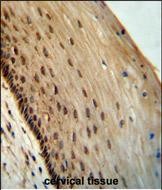

| IHC | 1/100-1/500 | Human,Mouse,Rat |

The SPDYE3 (Speedy/RINGO E3) antibody is a tool used to study the SPDYE3 protein, a member of the Speedy/RINGO family. These proteins are atypical activators of cyclin-dependent kinases (CDKs), bypassing the need for canonical cyclins to regulate cell cycle progression. SPDYE3. specifically, is implicated in cell proliferation and has been linked to cancer biology due to its overexpression in certain malignancies, such as cervical and hepatocellular carcinomas. It is also associated with viral infections, including HPV, where it may interact with viral oncoproteins to promote oncogenesis.

The SPDYE3 antibody enables researchers to detect and quantify SPDYE3 expression in cellular or tissue samples via techniques like Western blotting, immunohistochemistry (IHC), or immunofluorescence (IF). Its specificity is critical for distinguishing SPDYE3 from other Speedy/RINGO family members, which share structural similarities but may have divergent functions. Validated antibodies are essential to explore SPDYE3’s role in cell cycle dysregulation, tumorigenesis, and therapeutic resistance. Recent studies suggest SPDYE3 could serve as a biomarker or therapeutic target, driving interest in its functional characterization. However, research on SPDYE3 remains limited compared to other family members, highlighting the need for reliable antibodies to advance mechanistic and clinical insights.